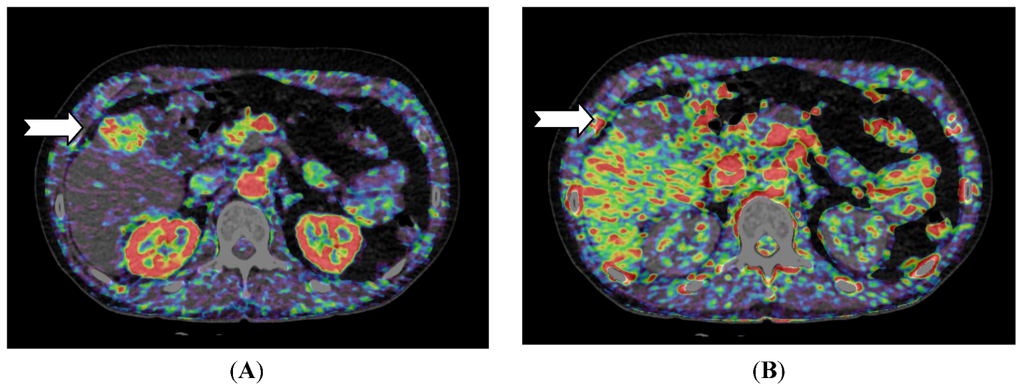

Figure 3.

CT perfusion examination of a 77-year-old female after right-sided portal vein embolization prior to liver resection. The patient has a large HCC in the right liver lobe and segment 4. (A) Perfusion shows the portal flow, which is eliminated on the right side and elevated in the left liver lobe; (B) Perfusion index (Arterial Flow/Arterial Flow + Portal Flow). This index is low in the left side due to elevated portal flow, and the index is high in all of the embolized segments, but highest in the vascular part of the HCC (arrow) (Images reconstructed with Vitrea 6.2, Vital Images A Toshiba Medical Systems Group).

For liver lesions, Miles et al. [20] first described liver perfusion using CT in 1991 analyzing one 10 mm section. With multidetector CT the entire liver can be covered with a single rotation using a 320-detector row scanner. Applying a dual input—single compartment model provides estimates of both arterial and portal perfusion [38]. Since the first report, several different liver perfusion studies have published. CT perfusion of the liver has demonstrated higher arterial blood flow in cirrhotic patients [39,40] and CT perfusion has been used to characterize hepatocellular carcinoma and to examine for residual tumor after transarterial chemoembolization (TACE) (Figure 2 and Figure 3) [41].